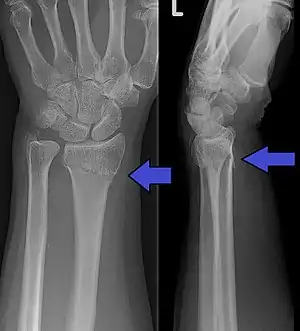

A distal radius fracture, also known as wrist fracture, is a break of the part of the radius bone which is close to the wrist.[1] Symptoms include pain, bruising, and rapid-onset swelling.[1] The wrist may be deformed.[1] The ulna bone may also be broken.[1]

In younger people, these fractures typically occur during sports or a motor vehicle collision.[2] In older people, the most common cause is falling on an outstretched hand.[2] Specific types include Colles, Smith, Barton, and Chauffeur's fractures.[2] The diagnosis is generally suspected based on symptoms and confirmed with X-rays.[1]

Diagnosis may be evident clinically when the distal radius is deformed, but should be confirmed by X-ray. The differential diagnosis includes scaphoid fractures and wrist dislocations, which can also co-exist with a distal radius fracture. Occasionally, fractures may not be seen on X-rays immediately after the injury. Delayed X-rays, X-ray computed tomography (CT scan), or Magnetic resonance imaging (MRI) can confirm the diagnosis.

Medical imaging

X-ray of the affected wrist is required if a fracture is suspected. Posteroanterior, lateral, and oblique views can be used together to describe the fracture.[5] X-ray of the uninjured wrist should also be taken to determine if any normal anatomic variations exist before surgery.[5]